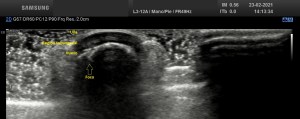

5

En la imagen 5 ves el típico aspecto de un vaso de alto flujo, lo normal, ya que tenía latido. Vas a ver dicho espectro con aspecto de picos y valles muy marcados, el sonido también es diferencial, puedes ver el doppler espectral y escucharlo. Su sonido y su aspecto es distinto del de una vena.

En este caso debí usar una muestra, flecha amarilla de la imagen 5, lo más pequeña posible, ya que el vaso lo era igual, adaptaremos esta muestra al tamaño del vaso que quieras estudiar. si la muestra no es la idónea la lectura puede ser incoherente. La muestra es el tamaño del «roi2 que hará el registro de la zona a estudio. Te enlazo arriba para que revises nociones básicas de doppler en post anteriores, también puedes consultar el índice del blog al final de este Post.